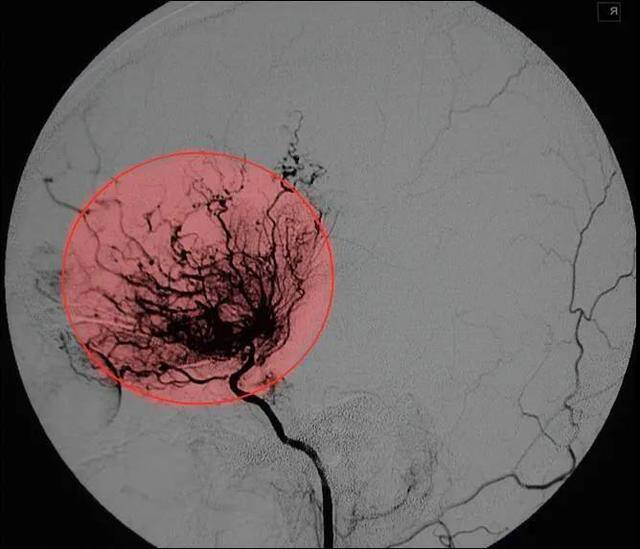

烟雾病是一种罕见的脑血管疾病,它的特点是不明原因的颅底脑血管狭窄闭塞,并在颅底新生很多细小的代偿血管,它特殊的名字源自于血管造影(DSA)检查的结果,通过血管造影,可以看到颅底大血管狭窄闭塞的同时周围新生的小血管像一缕缕青烟一样密集且混乱,因此而得名烟雾病。